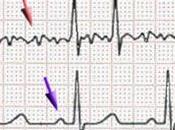

Lo dejamos en Fibrilación...

Tras marcar el número de teléfono…-. Hola, pregunto por Nicolás...?-. Hola, es Ud. el Doctor, ¿verdad?-. Eso es, Nicolás… Buenas tardes…... Leer el resto